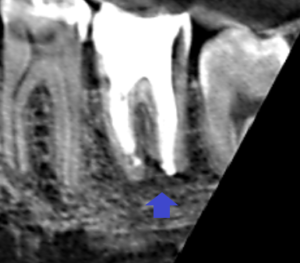

下顎大臼歯の矢状断のCT画像です。

矢印の先に膿の影がみられます。遠心根の先が吸収され、平らになっています。

膿が長くあった可能性が高いケースです。

もう既に根尖孔外感染を起こし治りにくい膿に代わっている可能性があります。